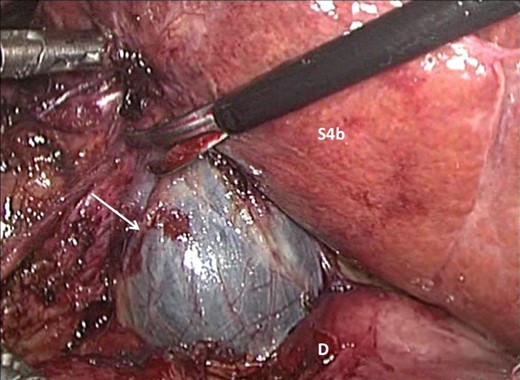

A laparoscopic completion cholecystectomy was performed. There were multiple dense adhesions that precluded visualization of the gallbladder remnant (Fig. 2). Meticulous dissection with cautery attached to ‘hot scissors’ eventually presented the gallbladder remnant (Fig. 3). Scarring at Calot's triangle prevented retrograde dissection, so the ‘dome down’ technique was used to identify cystic duct (CD) (Fig. 4) and right hepatic structures at the floor of an open-type Rouviere's sulcus (Fig. 5). Intraoperative cholangiography was performed via the CD using a 5Fr infant feeding (Fig. 6) and confirmed that: this structure was the CD, the extra-hepatic biliary tree was normal and there were no stones in the CBD (Fig. 7). At this point, the CD and artery were ligated and ‘hot scissors’ were used to separate the gallbladder remnant from the liver bed. This patient recovered uneventfully and remained asymptomatic 2 years later.

Multiple adhesions were present in the right upper quadrant preventing visualization of the gallbladder remnant.